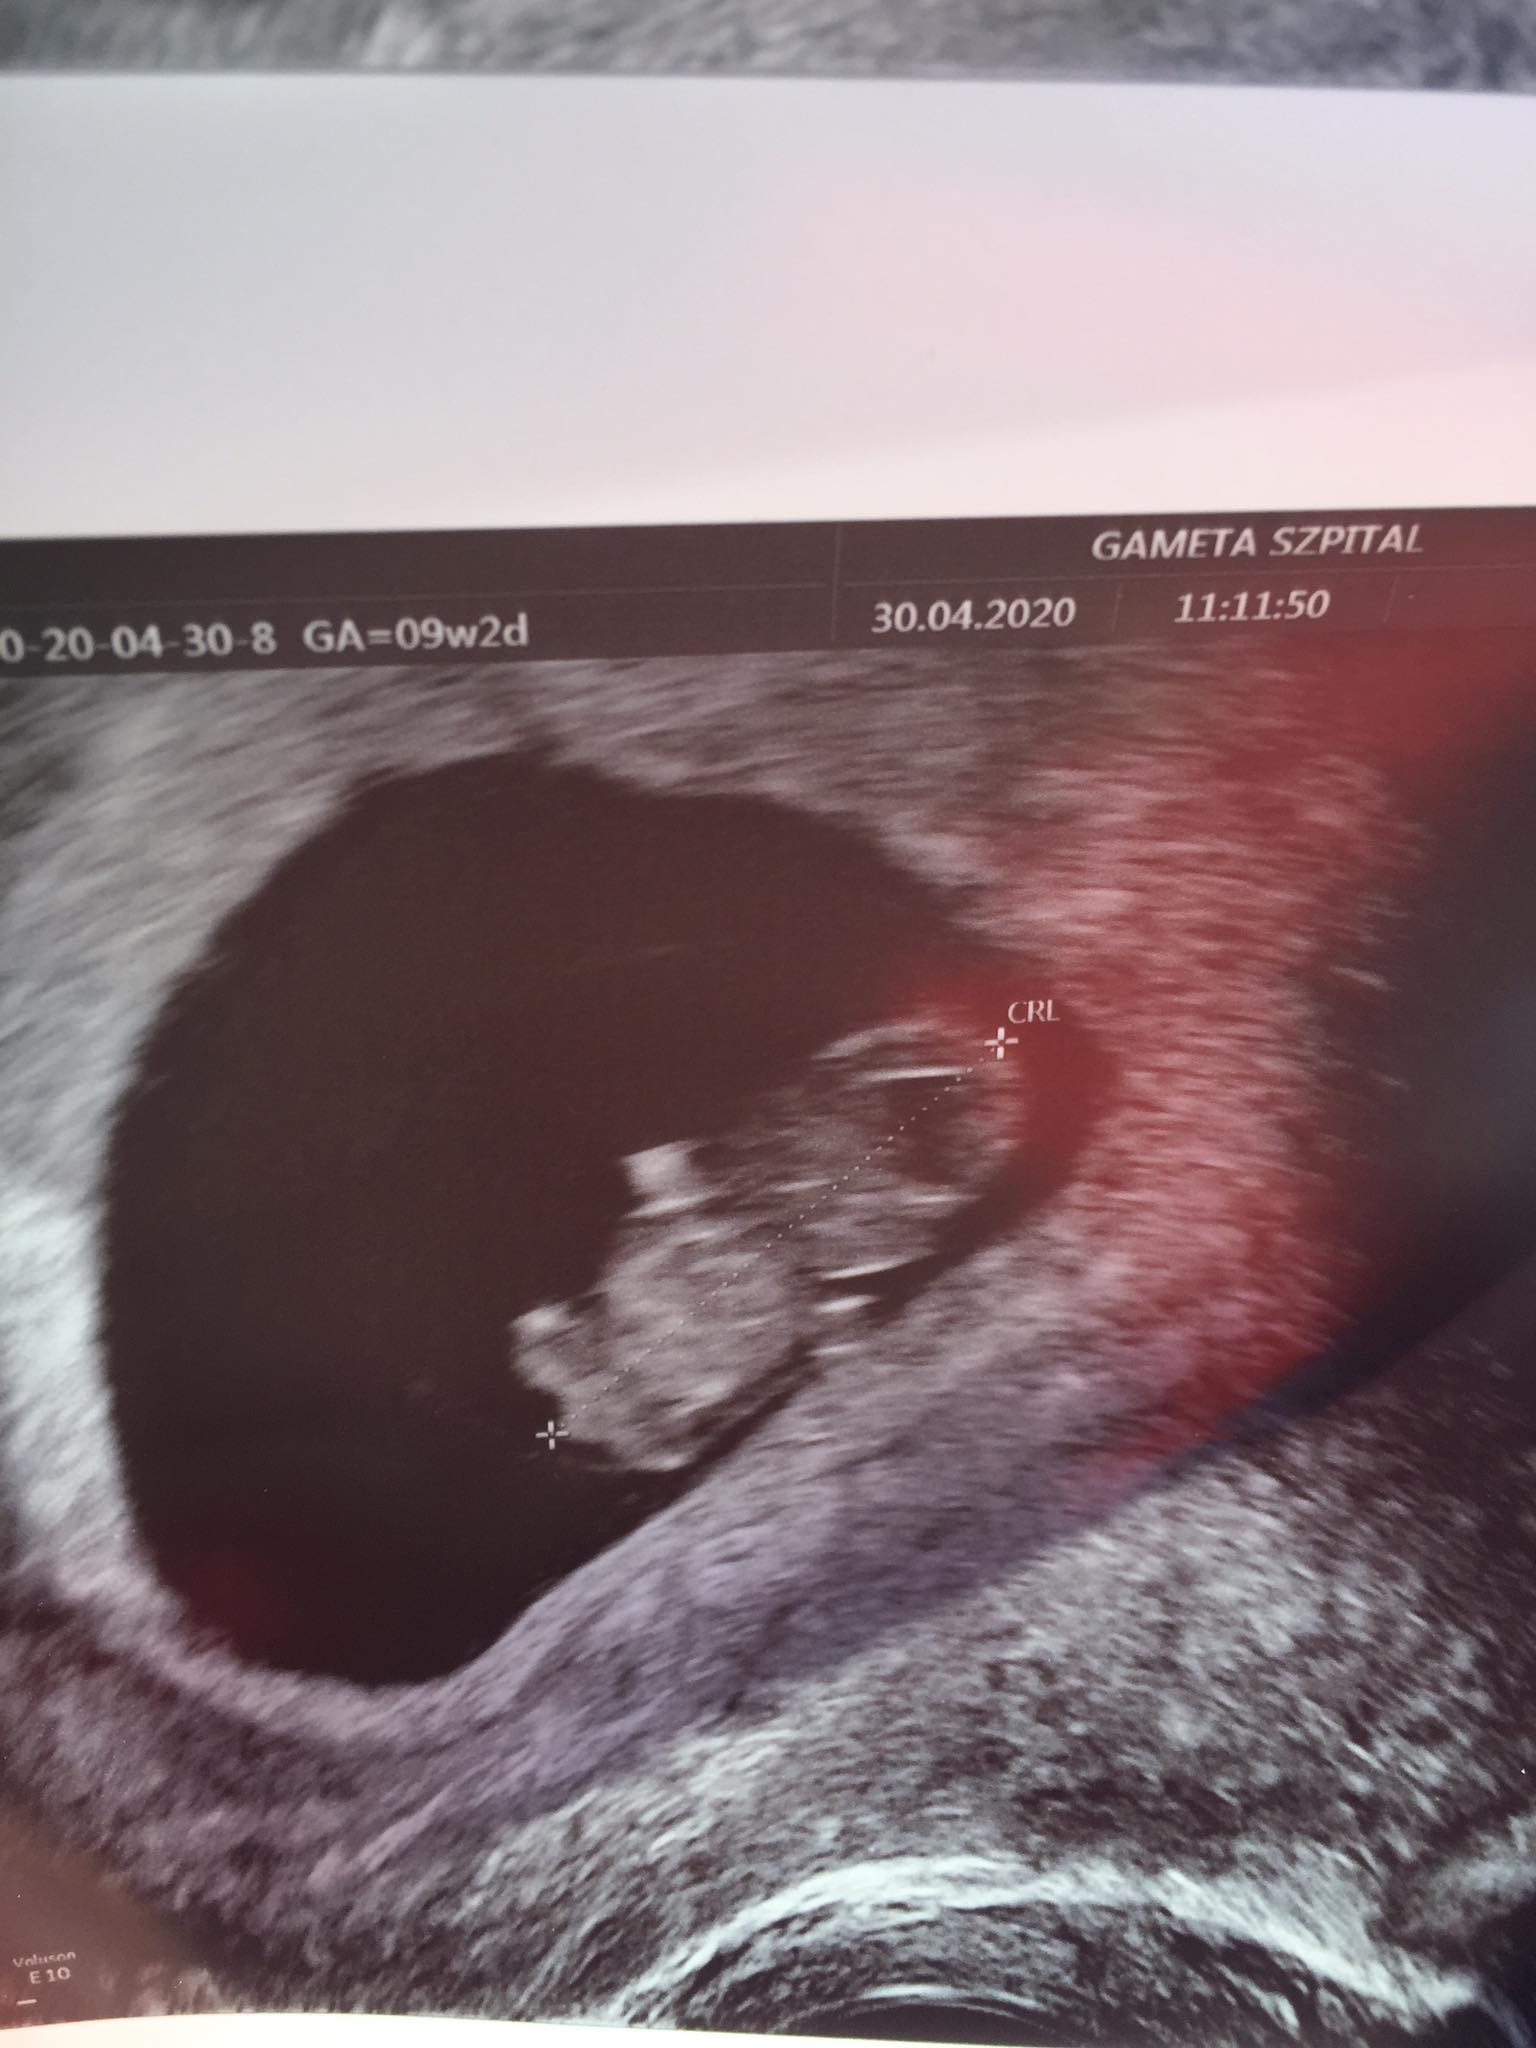

juz 9tc to chyba masz termin masz na sam poczatek grudnia?

Jaki slodki zarodek!